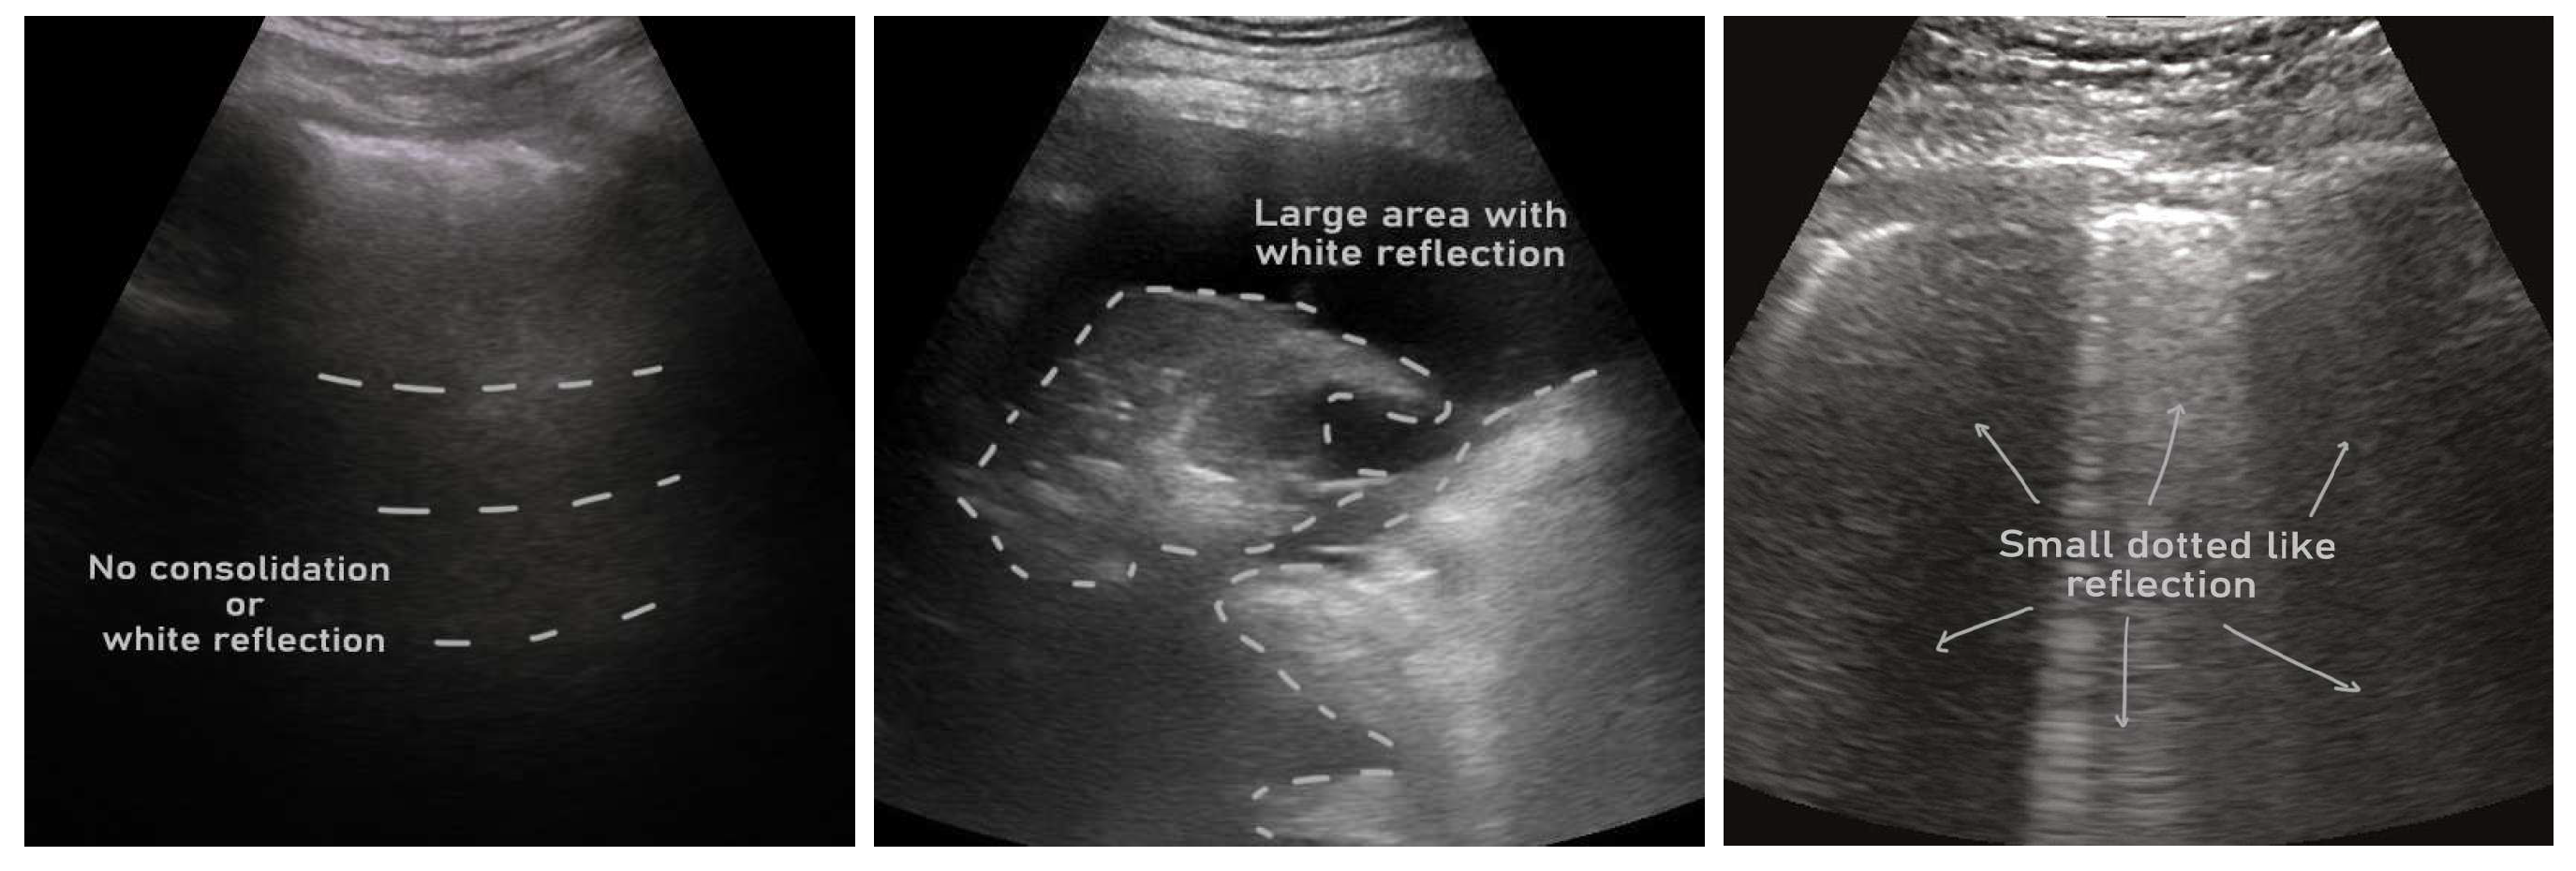

- ICLUS-DB: Soldati et al. [24] published an internationally standardized acquisition protocol and four-level scoring schemes for lung ultrasound (LUS) in March 2020. This dataset contains 277 ultrasound videos (consisting of 58,924 frames) of 17 confirmed COVID-19, 4 suspected COVID-19, and 14 healthy subjects. These data were collected at various clinical centers in Italy using various ultrasound scanners by either linear or convex probes. To evaluate the progress of pathology, this data consortium defined a four-level scoring system ranging from 0 to 3. The presence of continuous pleural-line and horizontal A-lines indicates a healthy lung with a score 0. Score 1 is tagged for initial abnormality when alterations in the pleural line appear. Score 2 is more severe than 1 and is associated with small consolidations in the lung. Score 3 is the most severe grade, which is associated with the presence of a larger hyperechogenic area below the pleural surface (i.e., white lung).